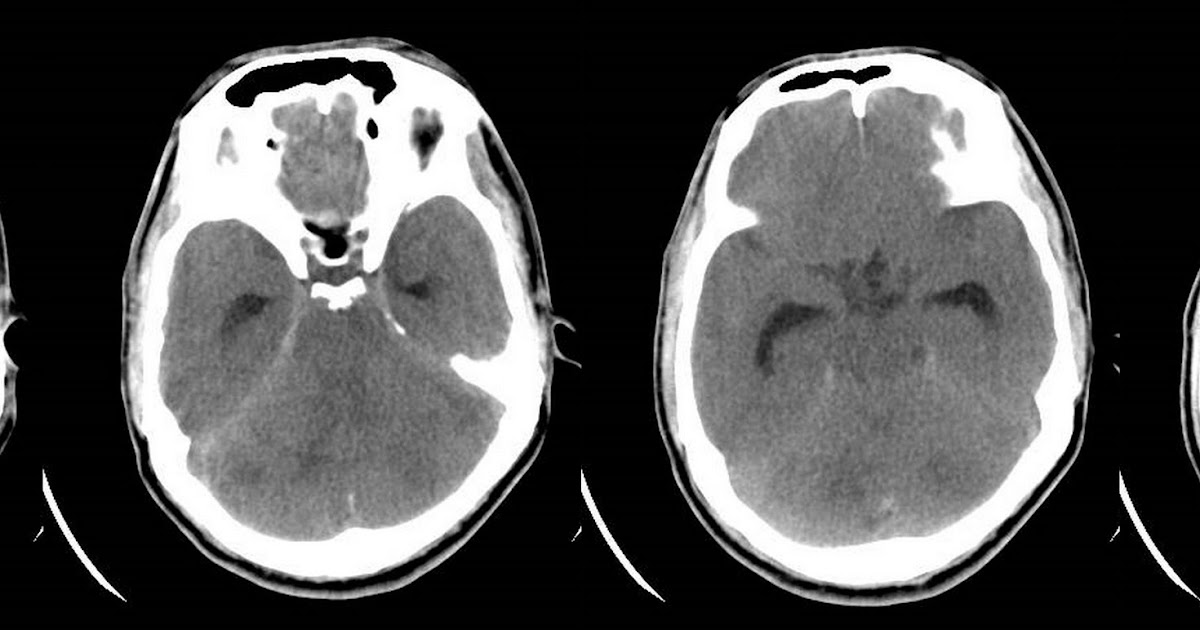

Субдуральный абсцесс

Субдуральный абсцесс 108 фотографий